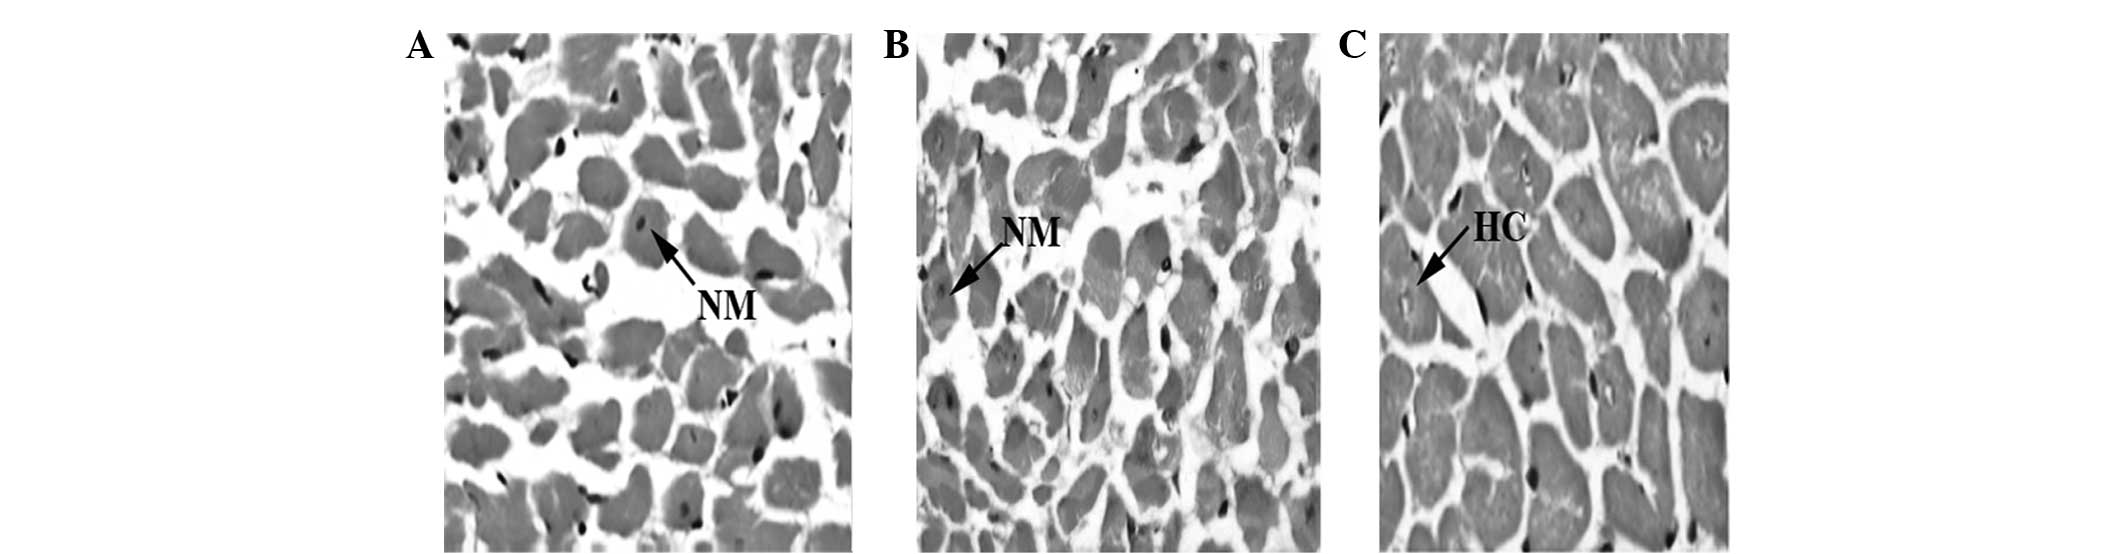

Effect of tanshinone IIA on cardiomyocyte hypertrophy and apoptosis in spontaneously hypertensive rats

In the present study, the effects of tanshinone IIA (TSN) on the prevention of left ventricular hypertrophy (LVH) and apoptotic processes were observed in spontaneously hypertensive rats (SHRs). A total of 18 SHRs (age, 8 weeks) were randomly divided into three groups. The SHRs in the control group (group S8) were sacrificed at week 8 of the experiment. The SHRs in the treatment group (group D18) and the placebo group (group S18) were injected with TSN and distilled water (1 ml/kg body weight/day), respectively, for 10 weeks, commencing at week 8, and were subsequently sacrificed at week 18. The systolic blood pressure (SBP) and left ventricular mass index (LVMI) were determined. Using hematoxylin and eosin and van Gieson staining, together with immunohistological methods, cardiomyocyte size and diameter, collagen volume fraction (CVF) and perivascular circumferential area (PVCA) were measured. Evaluation of Bcl‑2, Bax and p53 expression levels for apoptosis analysis was performed using western blotting. It was observed that the SBP, LVMI, cardiomyocyte size and diameter, CVF, PCVA and cardiomyocyte apoptosis index (Bax and p53 expression) were increased significantly in group S18 compared with group S8. However, Bcl‑2 expression levels were decreased in group S18 compared with group S8. The administration of TSN in group D18 resulted in higher Bcl‑2 expression levels and significantly decreased LVMI, cardiomyocyte size and diameter, CVF, PCVA, Bax and p53 expression levels compared with group S18. LVH and apoptosis of the cardiac tissues increased with the increasing age of the SHRs. TSN may inhibit the development of LVH and decrease the level of apoptosis in SHRs, possibly via the upregulation of Bcl‑2 and the downregulation of Bax and p53 expression.